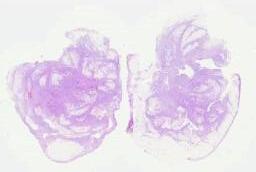

临床资料: 患者,女,34岁,病史:疑似“感冒”后咳嗽咳痰胸闷2周,影像CT:肺占位,生育史:孕3产3,一儿两女进行肺活检,两个月后心包多发结节,进行心包活检。